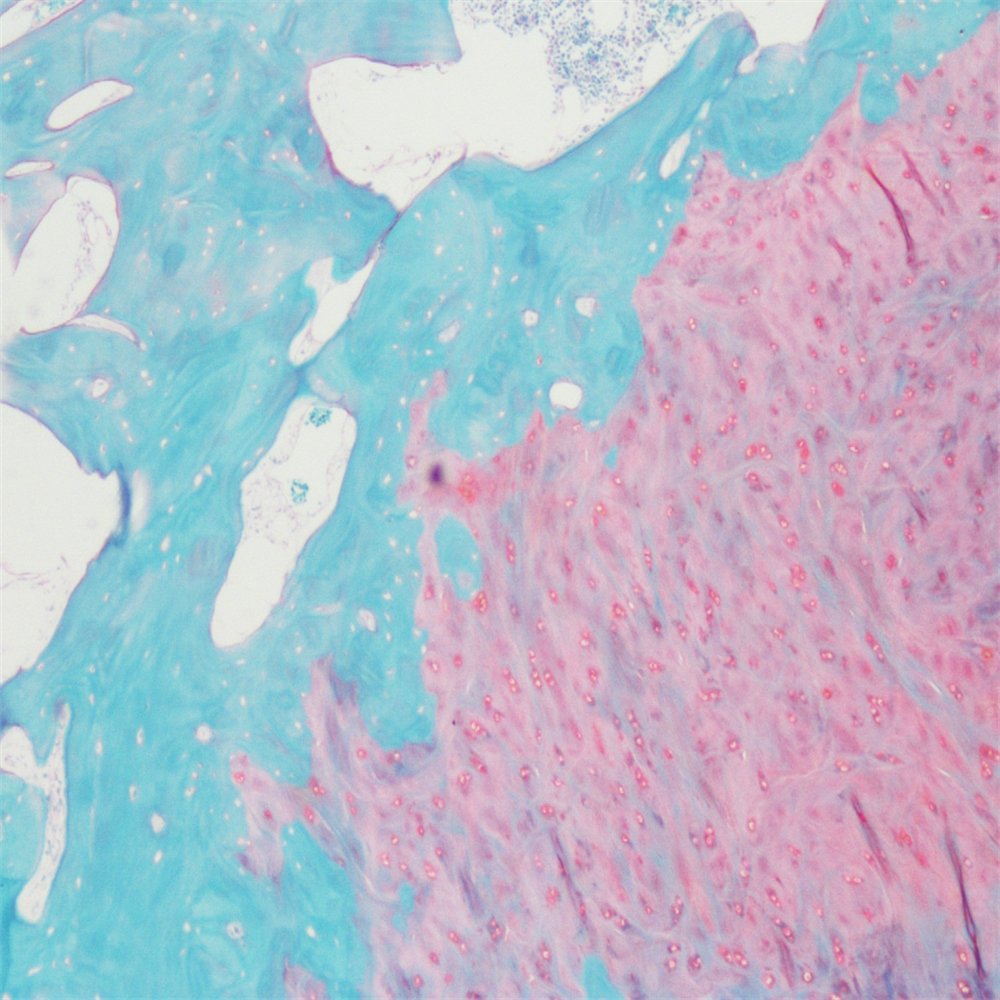

番红-固绿染色(软骨)在涉及关节软骨及软骨下骨的形态学研究中,常需联合使用多种染料以显示其组织学结构。其中,起源于上世纪60年代的番红O(safranin O)-固绿(fast green)染色因可以直观反映关节软骨、软骨下骨和骨组织的结构而备受青睐。软骨呈红色,成骨呈绿色。

番红-固绿(软骨)染色法的染色原理在于嗜碱性的软骨和碱性染料番红O结合呈现红色,嗜酸性的骨和酸性染料固绿结合而成绿色或者蓝色,与呈现红色的软骨对比鲜明,从而将软骨组织和骨组织区分开。番红O是一种结合多阴离子的阳离子染料,其显示软骨组织是基于阳离子染料与多糖中阴离子基团(硫酸软骨素或硫酸角质素)结合。番红O着色与阴离子的浓度近似成正比关系,间接反映基质中蛋白多糖的含量和分布。当软骨收到损伤时,软骨中的糖蛋白会释放出来,使基质成分分布不均匀,从而导致番红O淡染或不着色。通过图像分析软件可以对番红O染色的软骨基质进行定量分析。固绿与胶原纤维结合,不宜褪色。

<番红固绿-骨>